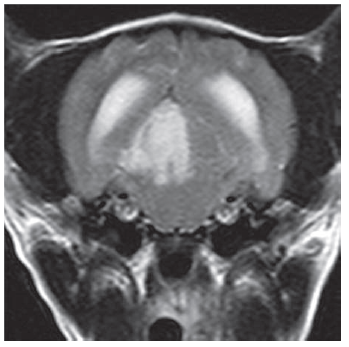

Name the areas marked with an asterisk and hash

A

• = suprapineal recess

# = quadrigeminal cistern